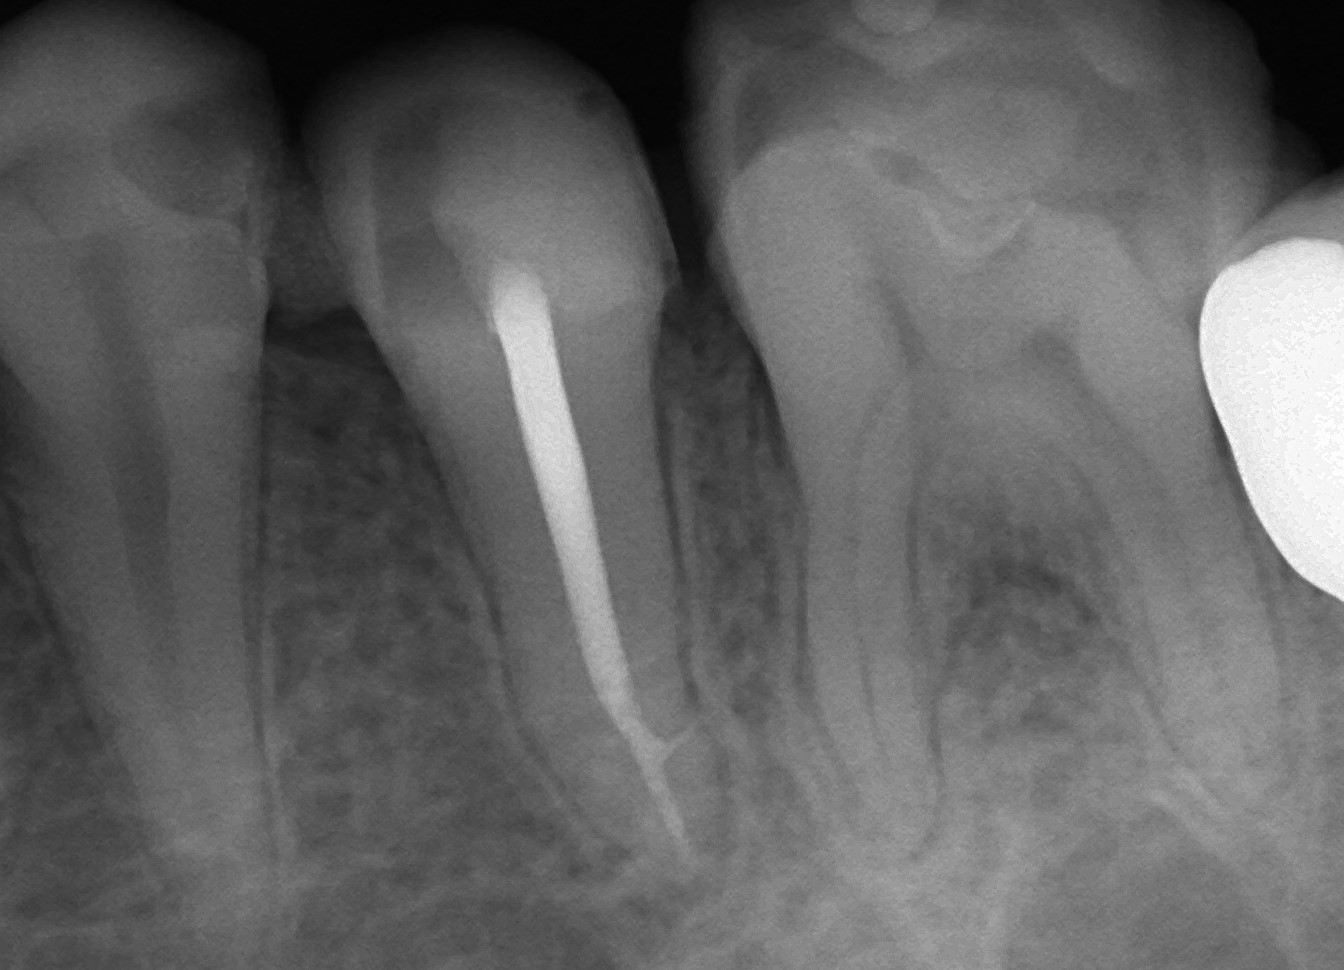

歯の根っこの枝分かれ

側枝って単語皆さんしってますか? 歯の神経の治療において厄介な存在で歯科医師の頭を悩ませる歯科用語の一つなんです。 このレントゲンにおいて根っこの先にお薬を詰めているんですが先が枝分かれになっているのわかりますか? これ […]